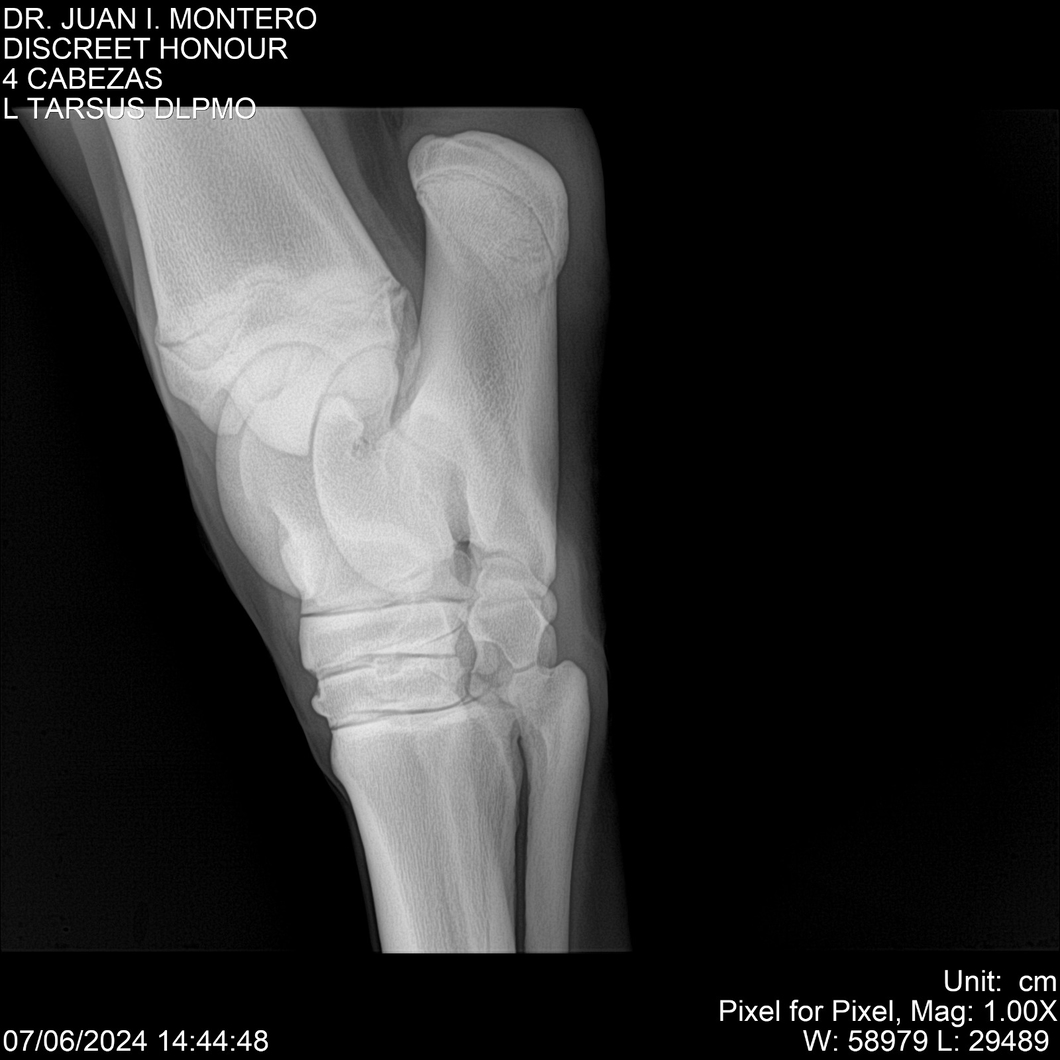

LOTE 6, DISCREET HONOUR 🔥 🔥 🔥 Lote Anterior Volver al remate Lote Siguiente Ficha Contacto Montevideo - Ficha del Lote Identificador: #281093 Categoría: Yeguarizos Montevideo - 82 Visualizaciones ClicData Contacto Empresa: Abelenda N. R., Walter Hugo Nombre*: Teléfono* : E-mail* : Mensaje Enviar Registrese gratis Este contenido Exclusivo está disponible sólo para usuarios registrados Ingresar